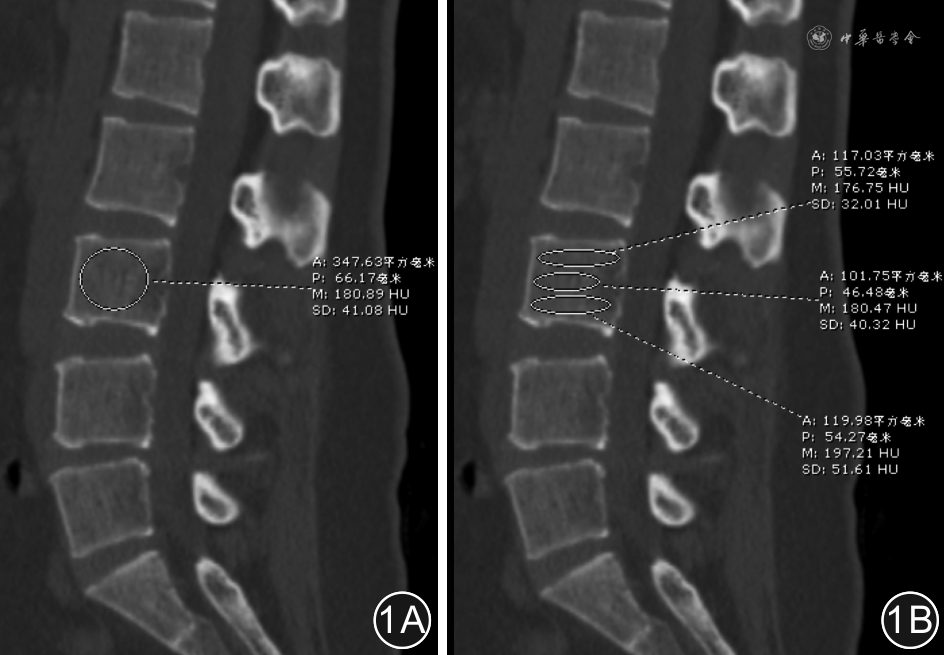

选择腰椎CT正中矢状位,采用Schreiber等[5]报道的方法测量椎体松质骨HU值:椎体整体HU值测量时,尽可能选择较大范围的松质骨构成ROI,排除皮质骨的干扰。椎体内不同部位HU值的测量,将椎体自上而下分为三等份,分别测量每一等份内松质骨的HU值,测量时尽可能选择较大范围的松质骨构成ROI,排除皮质骨的干扰。见图1。